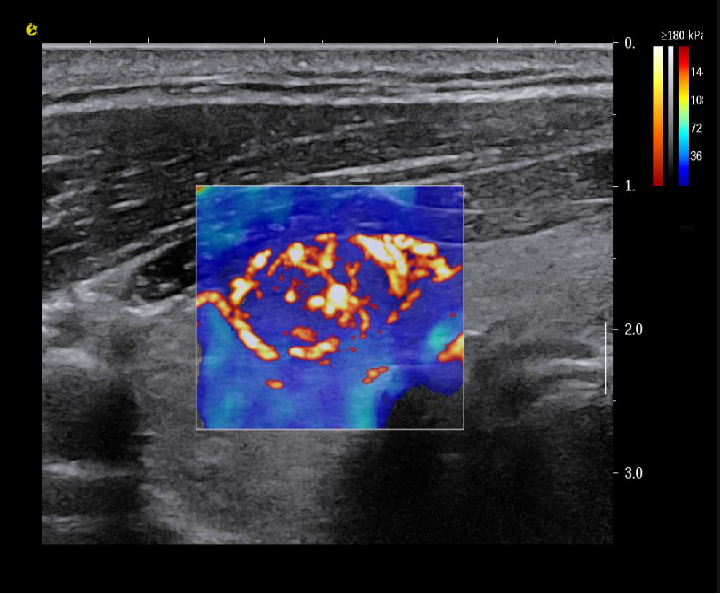

实时剪切波弹性成像

评估组织的软硬,并且提供定量数值,从而提示组织的良恶性。

鉴别诊断、精准分级、定量评价、穿刺引导、疗效评估、随访观察

image.png

恶性占位常常向周边组织进行侵润及扩散,二维很难观察到浸润部分的边界。使用实时剪切波成像能够对占位及周边组织进行硬度评估,通过颜色编码来区分不同组织的硬度信息,直观的观察占位组织的边界信息,更方便区分占位组织和正常组织的边界,准确评估消融范围。